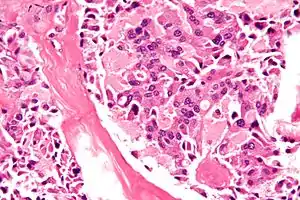

![]() Знімок медулярного раку щитоподібної залози – однієї з складових МЕН2Б. Фарбування Г-Е. Знімок медулярного раку щитоподібної залози – однієї з складових МЕН2Б. Фарбування Г-Е. | |